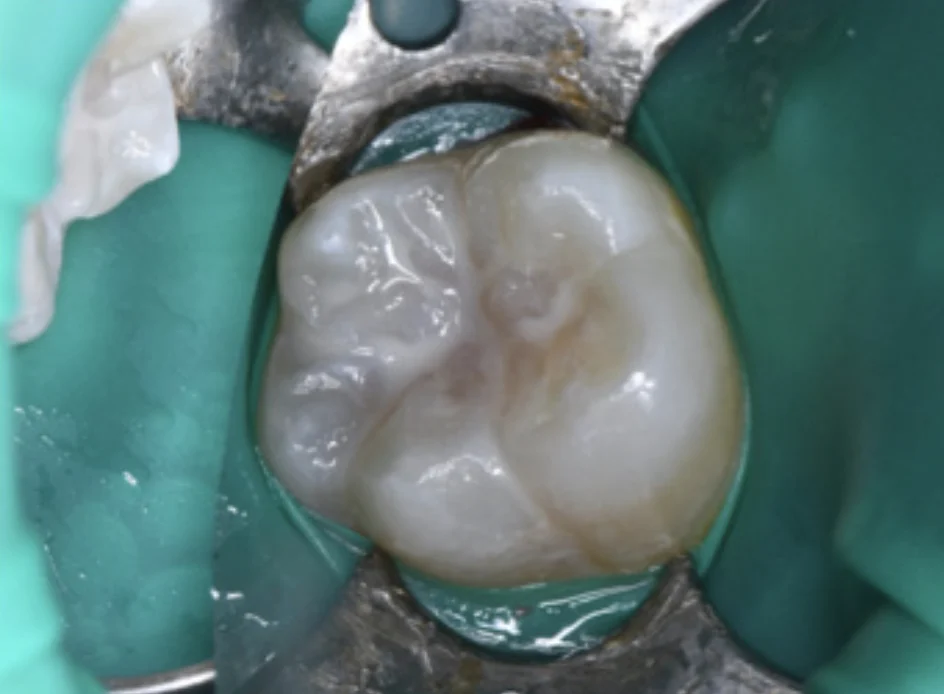

將顯示劑塗抹在牙齒表面,用清水漱口後,殘留在表面的粉紅色斑點就是牙菌斑,牙菌斑會導致蛀牙形成,用正確的刷牙方式,搭配牙線使用,去除牙菌斑就能有效防止蛀牙,並且注意哪些地方是平時不容易清潔到的死角,以後清潔時需要多加注意!